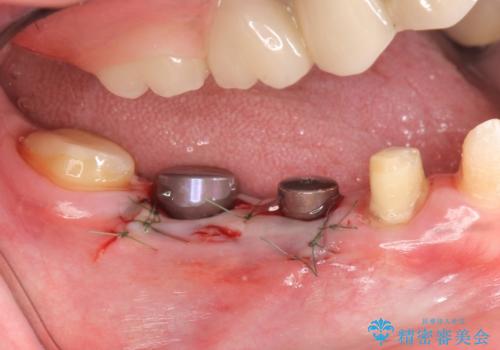

その後右下5、6番目にはインプラントを埋入し、右下3、4、5、6、7番の歯の補綴をオールセラミッククラウンによって行いました。

- オールセラミッククラウン…¥100,000×5、仮歯…¥10,000×5、インプラント(ストローマン)…¥200,000×2、カスタムアバット…¥100,000×2、骨増生…¥50,000費用は治療当時の料金となります

当院では主にストローマンという種類のインプラントを治療に用いています。

ストローマンは世界的にもNo1のシェアを誇り、骨との適合にも優れたインプラントです。